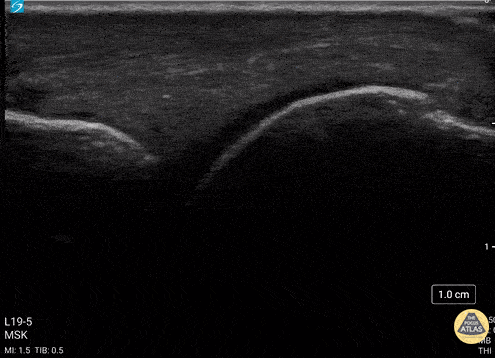

Musculoskeletal - Metacarpal Head Fracture

34 y/o M presented with fall while skiing injuring closed fist against ice and was found to have a displaced/impact fracture of his third metacarpal head. Video shows sagittal view scanning in the ulnar to radial direction at the third metacarpophalangeal joint (right is proximal). There is diffuse disruption of the cortex of the radial aspect of the metacarpal head and displaced/impaction fracture of the metacarpal head. Usually this surface should appear smooth. Articular cartilage can be seen as anechoic at the interface between the two bones. This defect was not visualized on initial or 2 week post x-ray, so ultrasound was able to guide the clinical team to appropriately splint and manage as a fracture. Eben Alexander, DO Devesh Patel, MD Eastern Virginia Medical School